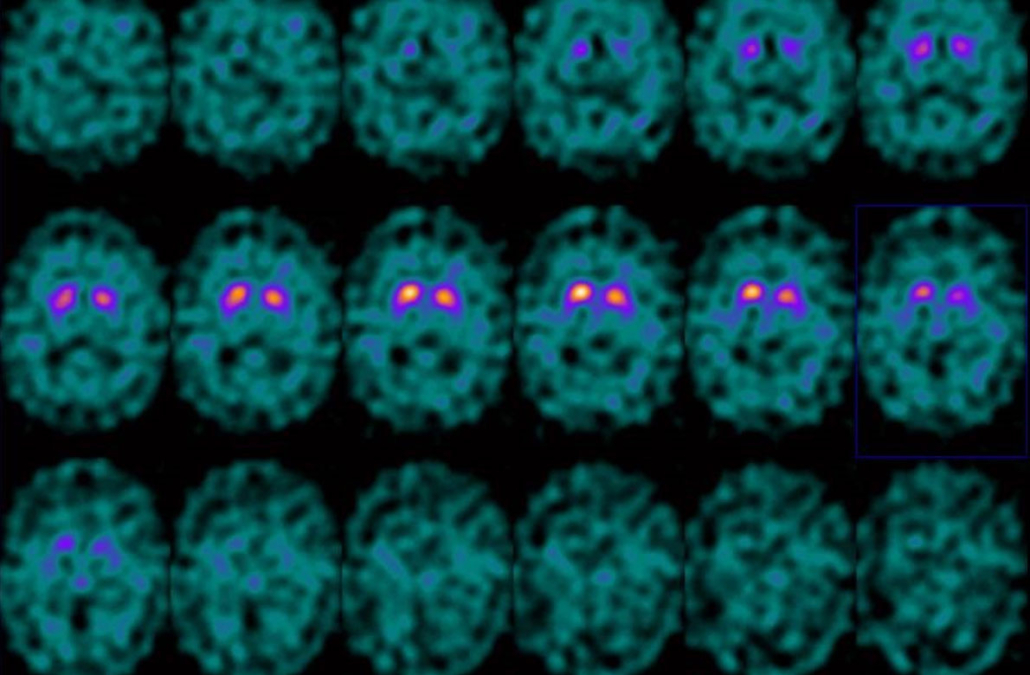

En algunas ocasiones, la causa de estos trastornos es algún fármaco o tóxico al que se ha estado expuesto. En otras, se debe a lesiones estratégicas en el sistema nervioso, ya sea por traumatismos, a consecuencia de un ictus, o de causa neurodegenerativa o genética. En todos los casos, un correcto diagnóstico primero sindrómico, que permita orientar correctamente las pruebas diagnósticas necesarias, y con ellas posteriormente un diagnóstico etiológico (de la causa), nos darán la oportunidad de tomar las medidas adecuadas para curar o, si esto no es posible, aliviar los síntomas y enlentecer la progresión de la enfermedad.